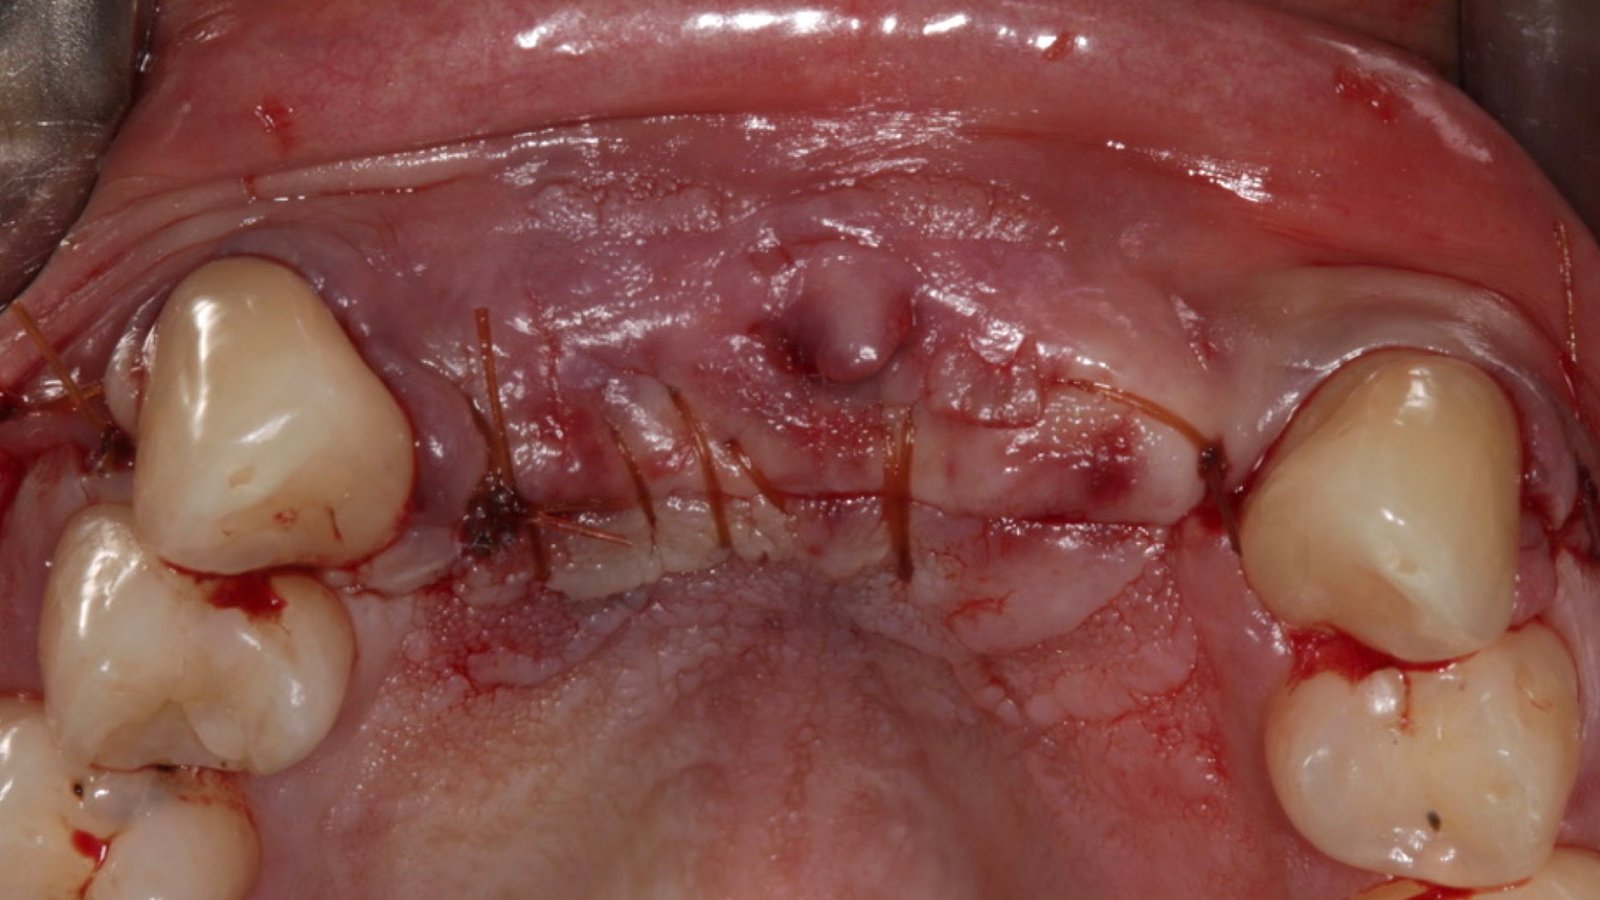

Paciente apresentou-se a Área de CBMF da Instituição com a pré-maxila edêntula (Figuras 1, 2 e 3) e foi submetido a técnica Screw Tent Pole utilizando os parafusos da linha Orth – Implacil de Bortolli (Figura 3). Do lado direito da pré-maxila foram instalados 3 parafusos que apresentavam roscas em toda superfície, enquanto que do lado esquerdo foram instalados 3 parafusos que não apresentam roscas no terço cervical (Figuras 4, 5, 6, 7 e 8). Biomaterial associado com PRF (Stick Bone) foi adequadamente acomodado na região e recoberto por membranas de PRF (Figuras 9, 10 e 11). Uma sutura livre de tensão foi realizada para finalizar o procedimento cirúrgico (Figuras 12 e 13).